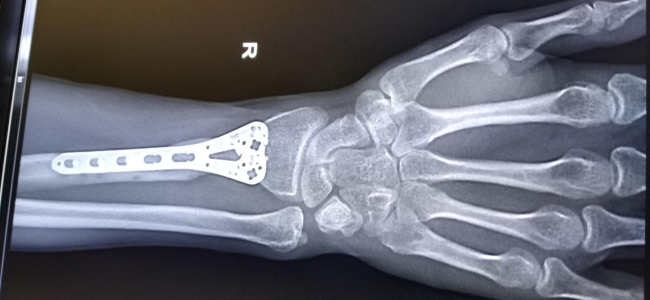

Kalau Anda habis mengalami benturan dan cedera, gejala penyakit tulang, atau mengetahui ada faktor genetik dan riwayat kesehatan yang menimbulkan risiko penyakit tulang maka segera lakukan pemeriksaan kepadatan tulang dengan dokter. Biasanya dokter akan melakukan foto rontgen untuk melihat sejauh mana kepadatan dan kekuatan tulang Anda.